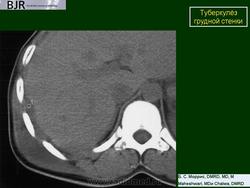

Туберкулёз грудной стенки. Ср, 13/12/2017 - 21:33 #1 Катенёв Валенти... Не на сайте Был на сайте: 7 лет 6 месяцев назад Зарегистрирован: 22.03.2008 - 22:15 Публикации: 54876 Рисунок 21.17 Туберкулезный остеомиелит с участием грудины

Рисунок 21.17